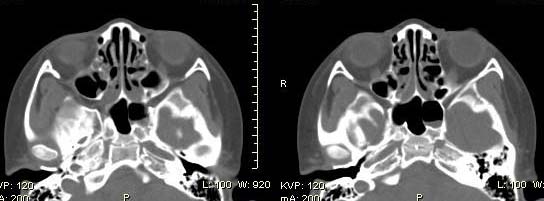

以下是引用随光逐影在2009-6-4 21:13:00的发言:[br]1)考虑鼻咽腺样体重度肥大。2)双侧鼻腔炎性改变。3)双侧上颌窦、双侧筛窦及左侧蝶窦炎症。

以下是引用zsl6918在2009-6-5 7:42:00的发言:[br]首先考虑鼻咽腺样体重度肥大,鉴别纤维血管瘤.强化有助明确.